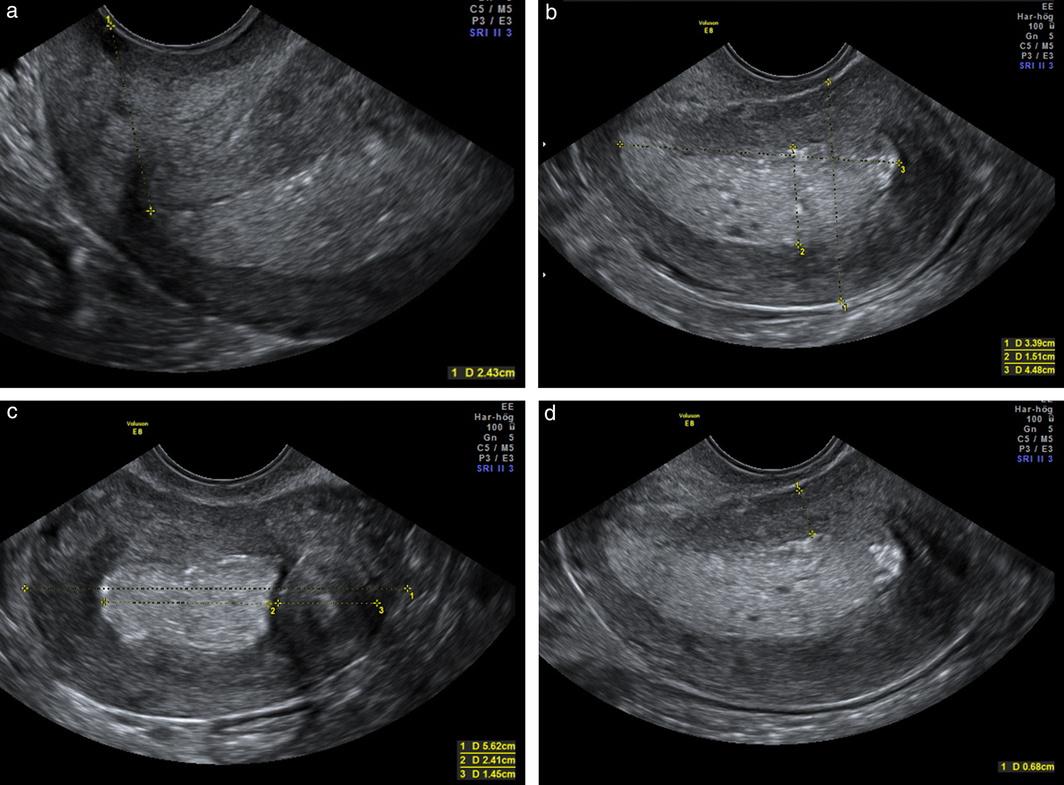

During an ultrasound for uterine cancer, a healthcare provider will use a handheld device called a transducer to send sound waves through the body. The sound waves bounce off the organs and create an image on a computer screen. The healthcare provider may also use a special wand called a transvaginal ultrasound probe, which is inserted into the vagina to obtain more detailed imagesoftheuterusandovaries.

Ultrasound can help detect abnormalities in the size, shape, or texture of the uterus or other reproductive organs, which may indicate the presenceofcancer.Itcanalsohelpdeterminethe stage of the cancer and whether it has spread to nearbyorgansortissues.